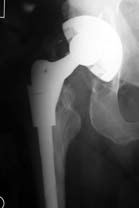

The Apex ARC™ Neck Sparing Stem

- Modular junction failures = 0

- Stem revisions = 2

|

Explanted stem |

One stem removed for sepsis.

One removed for traumatic dislocation, converted to an Apex Modular Primary stem.

Female with a posterior dislocation poly exchanged from neutral liner to a 15º and an increase in 3.5 mm vertical height neck position into max 12º varus position.

Note: At the time of surgery a large soft tissue mass was found anteriorly and was thought to be associated with bowstringing of the anterior superior capsule as an unusual consequence of the posterior capsular repair.

The second case removed the neck for access to the socket (cup & poly replaced along with a new neck).